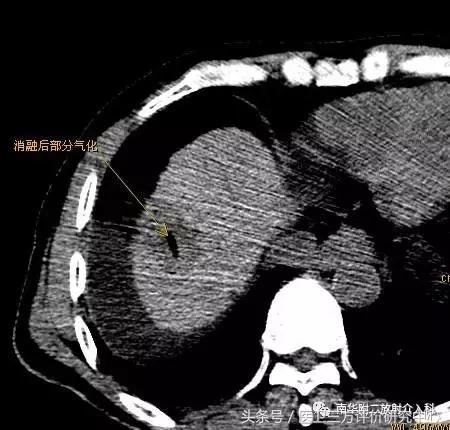

微波消融后局部改变(肿瘤坏死、气化)

患者曹某,男,63岁,有乙肝肝硬化,近3月来血AFP持续增高,我院CT及MRI增强扫描示肝SⅧ段占位,拟诊小肝癌,跟病人及家属商议后决定行微波消融治疗;遂于昨日下午在CT引导、局部+静脉联合麻醉下顺利完成了微波消融术治疗。手术时间约45分钟,术后患者未诉特殊不适,现恢复良好,已可下床自由行走。在此特别感谢麻醉科、消化内科及介入室老师的鼎力支持!